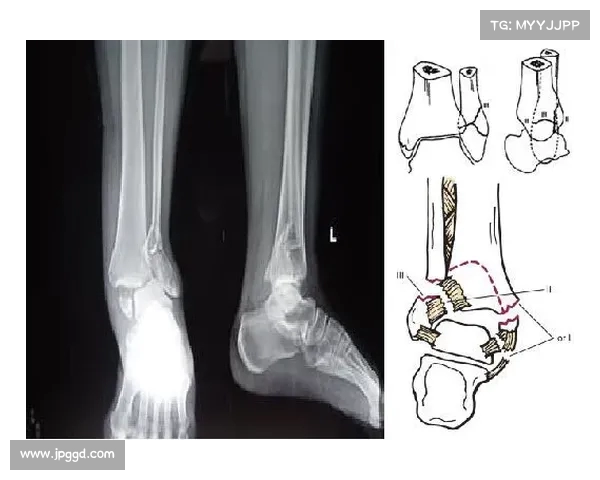

穆西亚拉的伤情可以分为两部分,首先是腓骨骨折,其次是踝关节脱臼。腓骨骨折是指小腿上的腓骨发生断裂,这一部位的骨折通常会影响到运动员的稳定性和行走能力。由于腓骨在腿部骨架中的重要性,它的骨折不仅会影响肌肉力量的发挥,还可能会造成长期的康复过程。

踝关节脱臼则更为复杂,脱臼意味着关节的正常结构被破坏,导致关节骨骼位置的严重错位。这类伤病通常需要通过手术矫正才能恢复,而手术后的康复过程也非常漫长。踝关节脱臼后,受伤部位的韧带和肌肉会受到极大的损伤,恢复过程充满了不确定性。结合腓骨骨折与踝关节脱臼的双重影响,穆西亚拉将面临一段长时间的缺席。

在伤病发生后的初期阶段,医生通过影像学检查确认了伤势的严重性,立刻安排了手术治疗。手术的目的是为了恢复腓骨和踝关节的结构,减少进一步损伤的风险。虽然手术过程相对常见,但穆西亚拉的年轻身体是否能够完全恢复,依然是一个未知数。治疗后,他还需要经过长期的康复训练,恢复期可能长达半年甚至更久。

穆西亚拉的治疗过程将是一个复杂且漫长的过程。首先,他需要接受腓骨的固定治疗,这通常包括手术中的钢钉或钢板植入,以确保骨头的稳定性。对于踝关节的治疗,医生可能会采用关节内固定的手段,帮助脱臼的关节恢复正常位置,并确保伤区不会受到进一步的压迫。